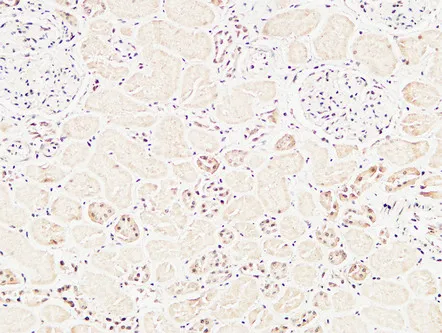

Cleaved-Caspase-8 (D384) Rabbit Polyclonal Antibody

Cat: APRab08968